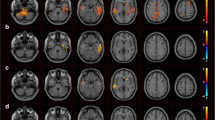

In the current study, decreased ReHo values were observed in the FES group compared with HC in the left medial frontal gyrus (MFG), right precentral gyrus, left STG, left middle temporal gyrus (MTG), and left thalamus (p < 0.01 for all, corrected by TFCE; Fig. 1 and Table 2). In contrast, increased ReHo values were found mainly in the left MFG, left inferior parietal lobule (IPL), left precuneus, and right lentiform nucleus (LN) in the FES group relative to HC (p < 0.01 for all, corrected by TFCE; Fig. 1 and Table 3). The comparison between the two groups was adjusted for age, gender, illness duration and the probability of gray matter as covariates. Then, the subsequent correlation analysis in patients was performed within the ReHo decrease mask and the ReHo increase mask, respectively.

Brain regions with significantly altered ReHo in schizophrenic patients compared to control subjects. Statistically significant differences in gray matter volume were defined as p < 0.01, TFCE corrected after correcting for age, gender, education, illness duration and the probability of gray matter. Warm color indicates that ReHo is higher in the schizophrenic patient group than in the healthy control group, and vice versa